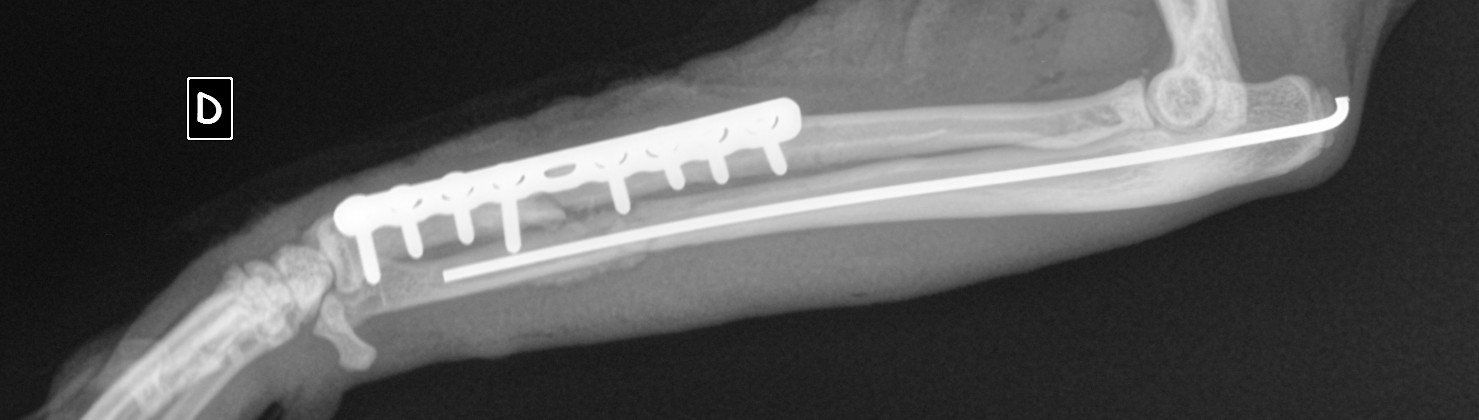

NOUGAT a été opéré de sa fracture fémorale. Les fractures du bassin quant à elles se cicatriseront toutes seules.

A sa présentation au vétérinaire, NOUGAT souffrait de nombreuses plaies d’abrasion, d’une double disjonction sacro-iliaque, d’une fracture pubienne et d’une fracture de Salter Harris de type I de la tête du fémur.

Les disjonctions sacro-iliaques droite et gauche se consolideront par elle-même avec l’observation d’une période de repos. En revanche, une intervention chirurgicale a été nécessaire afin de retirer la tête du fémur. Cela ne posera pas de problème pour sa vie future. Des soins de plaies ont également été faits tous les jours.